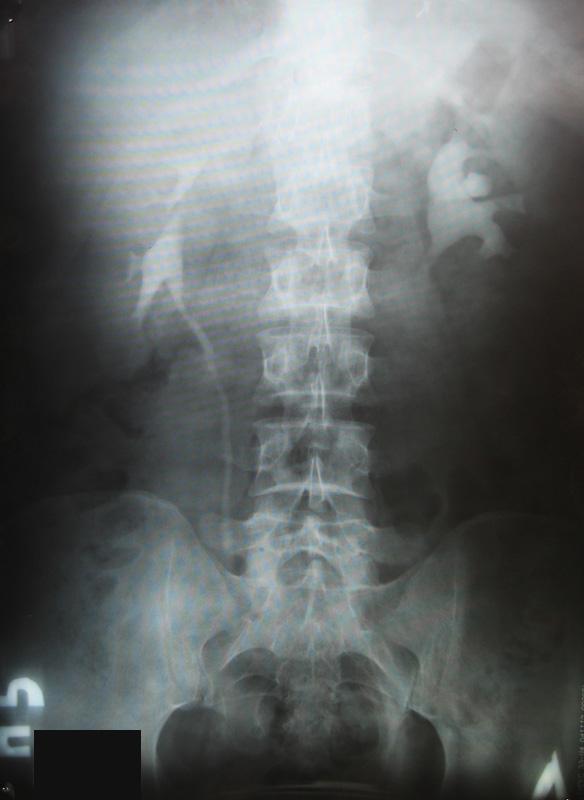

Посев мочи на флору и чувствительность к антибиотикам проводил - роста флоры не выявлено. Результаты урографии: http://s50.radikal.ru/i130/1005/fc/38ec99eeac78.jpg

У Вас гидронефротическая трансформация левой почки. Необходимо проведение ретроградной пиелографии в условиях урологического стационара. При обнаружении камня в мочеточнике - показано его лечение.